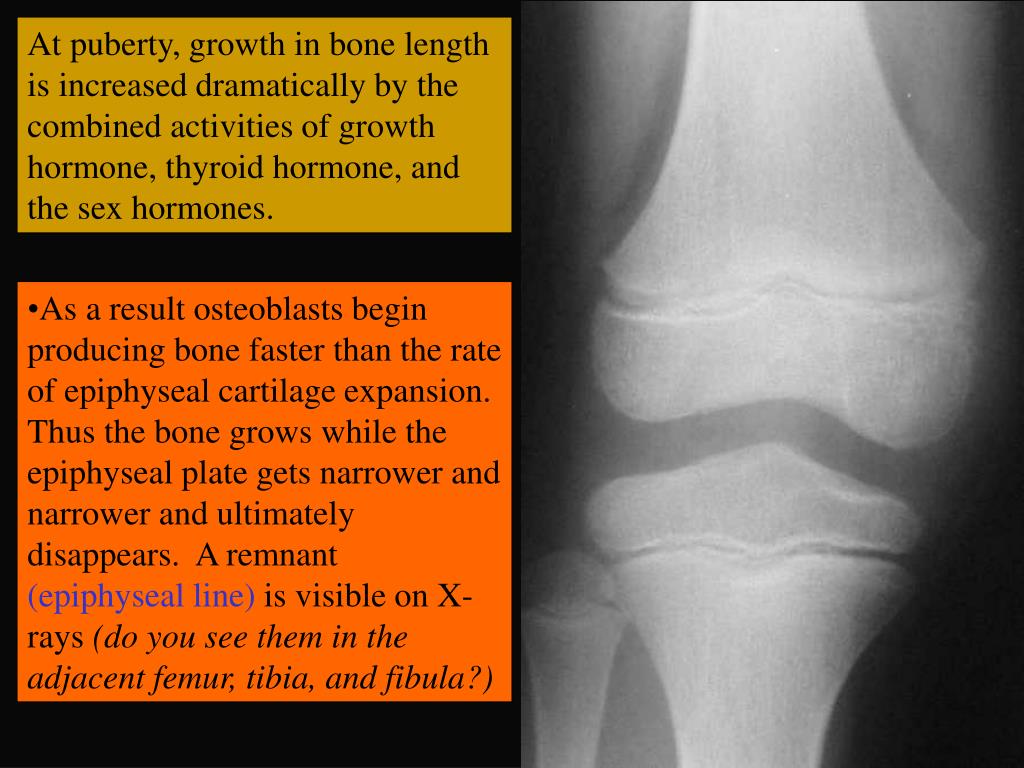

30. At puberty, growth in bone length is increased dramatically by the combined activities of growth hormone, thyroid hormone, and the sex hormones. • As a result osteoblasts begin producing bone faster than the rate of epiphyseal cartilage expansion. Thus the bone grows while the epiphyseal plate gets narrower and narrower and ultimately disappears. A remnant (epiphyseal line) is visible on X-rays (do you see them in the adjacent femur, tibia, and fibula?)